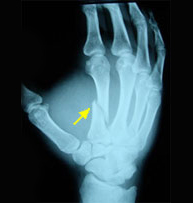

Las fracturas de los metacarpianos y las falanges suponen el 10% del total de todas las fracturas y más de la mitad se deben a traumatismos laborales. Es indiscutible la importancia que tiene una mano en nuestra vida diaria y ni que decir tiene que su recuperación exige de un conocimiento de la anatomía y biomecánica exquisita para poder diagnosticar y tratar adecuadamente sus lesiones. Son muy frecuentes las rigideces por tratamientos inmovilizadoresprolongados por lo que proponemos técnicas mínimamente invasivas que permitan una movilización precoz y unareincorporación a la actividad cotidiana lo antes posible.